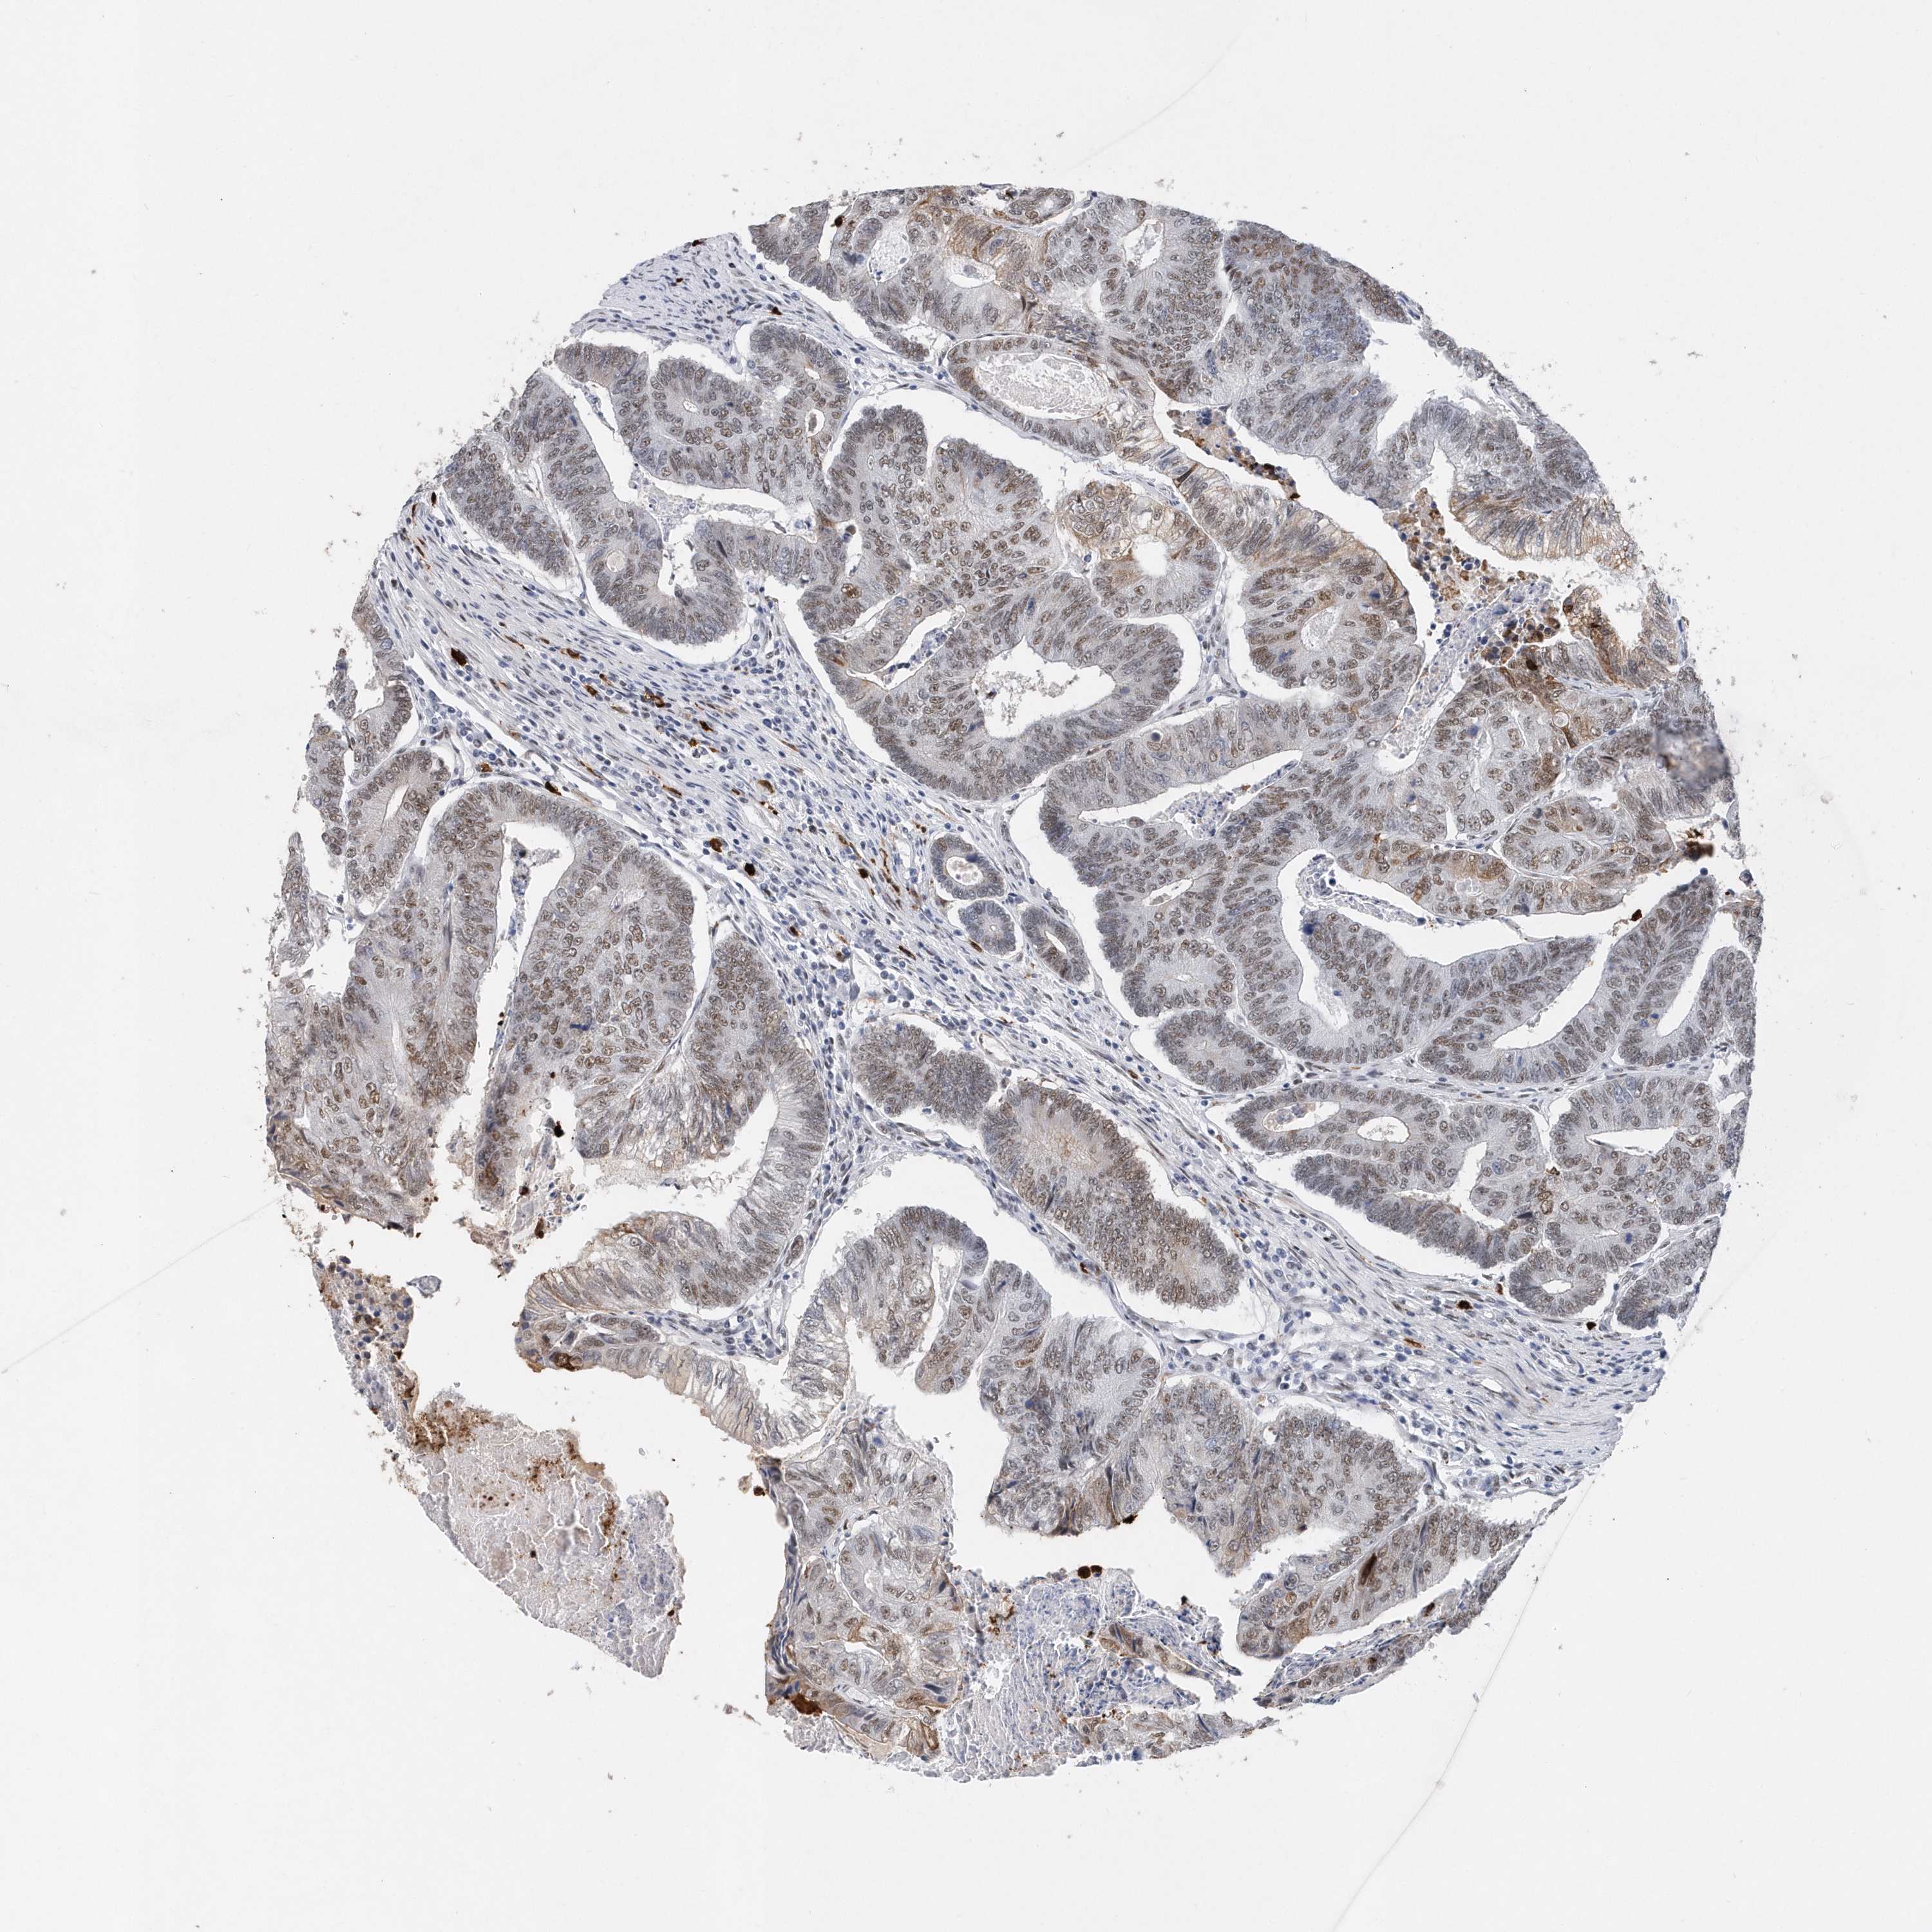

CANCER COLORECTAL CANCER Show tissue menu

Colorectal cancer

Human cancer

Colon adenocarcinoma